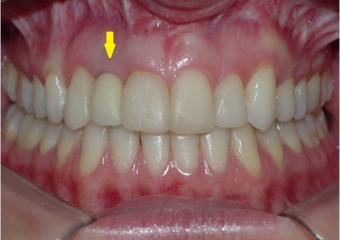

Imagem do caso após remoção do aparelho e instalação de prótese sobre implante em porcelana - Clínica Cliniface

Imagem do caso após remoção do aparelho e instalação de prótese sobre implante em porcelana